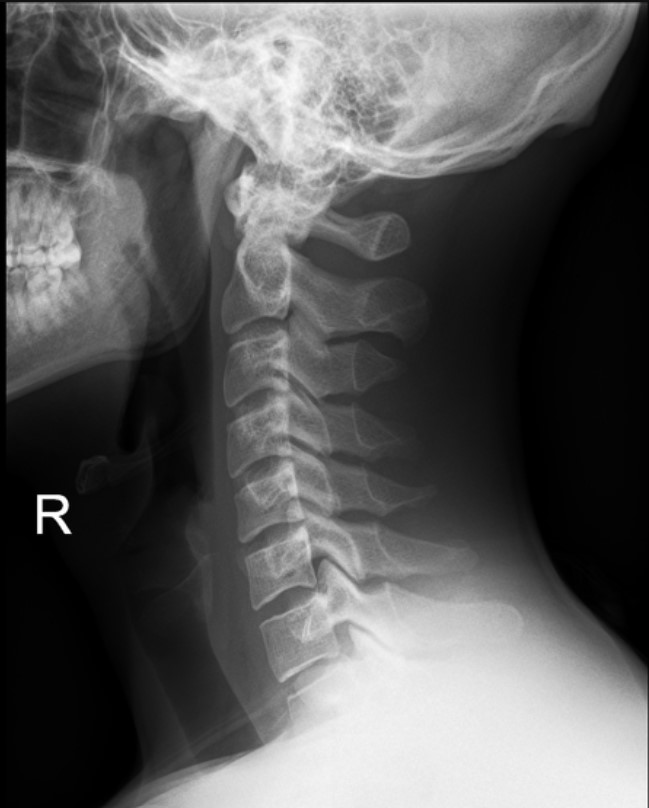

Normal Images Cervical Spine Lateral Xray Cervical Spine CT Cervical Spine MRI Sagittal Cervical Spine MRI Axial Lumbar Spine AP Xray Lumbar Spine Lateral Xray Lumbar Spine CT sagittal Lumbar Spine MRI sagittal Lumbar Spine MRI axial